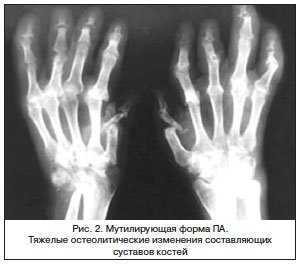

Мутилирующая форма ПА, как указывалось выше, проявляется тяжелыми остеолитическими изменениями составляющих суставов костей. Резорбции подвергаются не только эпифизы, но и диафизы костей суставов, вовлеченных в патологический процесс. Иногда поражение затрагивает не только все суставы кистей и стоп, но и диафизы костей предплечья (рис. 2).